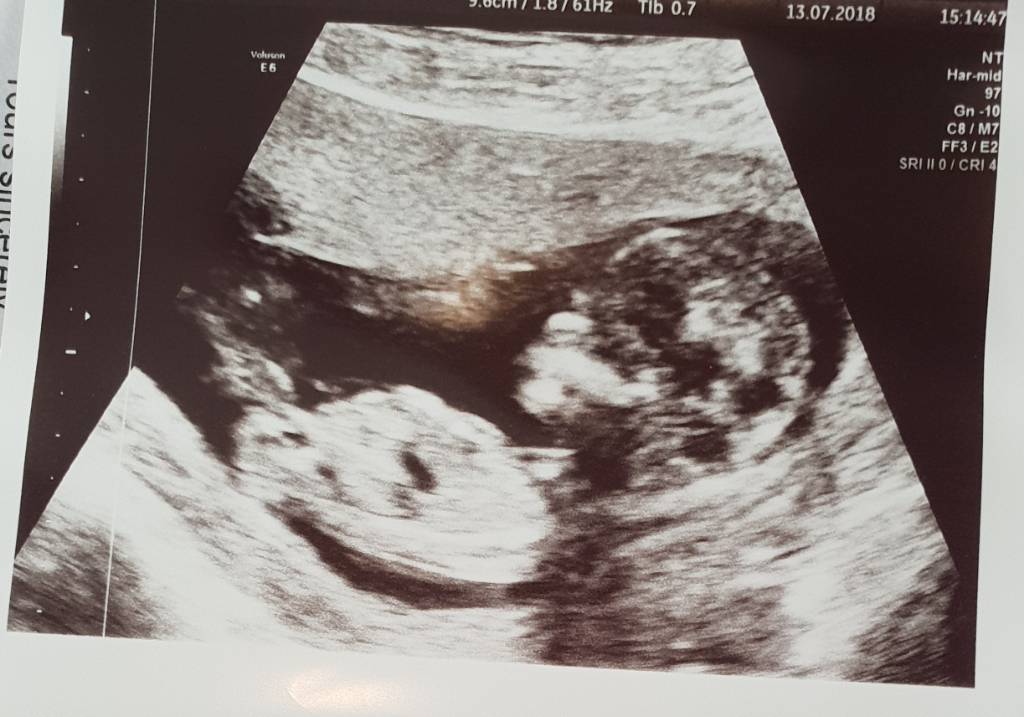

Update at 13.2 [emoji4]Attachment 39899Attachment 39900Attachment 39901